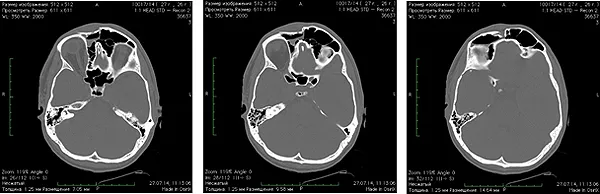

Спиральная компьютерная томография до операции: